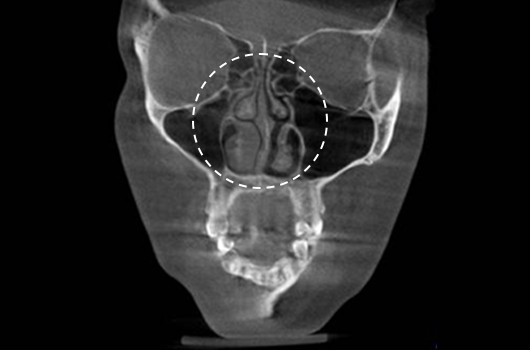

Operasi hidung CT 3D membantu pelaksanaan operasi hidung yang lebih canggih setelah menganalisis wajah secara cermat untuk menentukan mana yang terbaik.Analisis tiga dimensi digunakan untuk mengetahui keadaan secara umum, ukuran, bentuk, dan asimetri tulang hidung, tulang rawan septum hidung, dan jaringan kulit, yang tidak dapat ditentukan melalui konsultasi pada umumnya. Saat merencanakan revisi operasi hidung, kami dapat memeriksa elemen fungsional seperti deviasi septum hidung, bentuk implan yang ada, termasuk implan silikon, atau komplikasi dari operasi sebelumnya.

Pentingnya 3D-CT Scan pada Operasi Hidung

Dalam setiap konsultasi operasi hidung, Klinik Operasi Plastik Braun menggunakan 3D-CT scan untuk menganalisis isu-isu berikut dalam tiga dimensi: Rancangan bedah dapat dibuat lebih tepat dan potensi efek samping dapat berkurang dengan memahami lebih lanjut ukuran, bentuk, dan asimetri bagian hidung yang tak kasat mata dan struktur anatomi disekitarnya sebelum operasi.

1. Analisis tulang rawan septum dalam berbagai ukuran dan bentuk

2. Diagnosis dan tindakan untuk deviasi hidung dan deviasi septal

3. Analisis untuk lebar dan asimetri tulang hidung

4. Diagnosis Inferior turbinate asymametry dan pembedahan hidung tersumbat